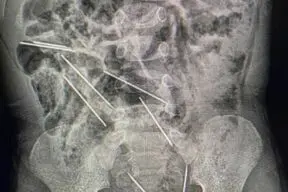

As agulhas no corpo da criança estavam em diversos locais do intestino, próximo a bexiga e outros

"Foram extraídas as oito agulhas, das quais duas estavam no lado direito do peritoneu, três no lado esquerdo, uma na parede abdominal e outras duas entre a bexiga e o recto", explicou o cirurgião.